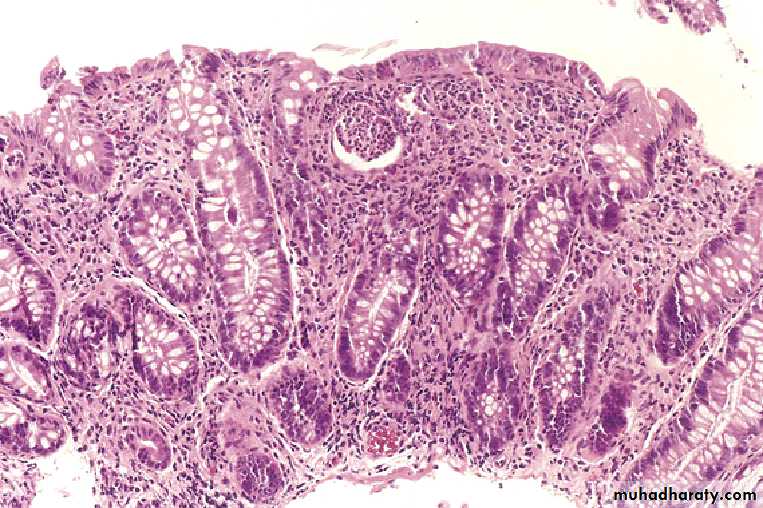

crypt abscesses (microabscesses) and crypt distortion

Pseudopolyp

Ulcerative Colitis

Pseudopolyps

PSEUDOPOLYPSCrypt Abscess